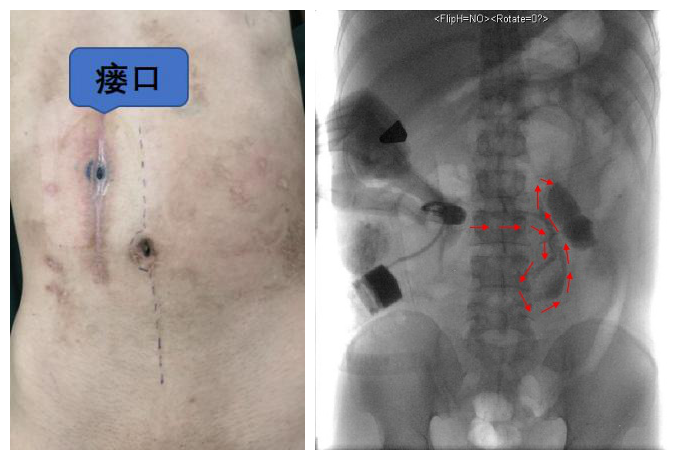

腹部瘘口情况                                           造影提示瘘道

随后,李元新团队根据患者的肠瘘特点,制订了“切除肠瘘+吻合”的手术方案。顺利气管插管麻醉后,因为腹部外伤、既往手术史,导致患者腹腔致密粘连,李元新完全游离整个肠道,实施全消化道肠粘连松解术,进而切除肠瘘肠段并行肠吻合术,恢复消化道的连续性、完整性和功能性。同时,李元新还为患者实施了北京清华长庚医院胃肠外科的特色技术——小肠排列固定术,大大降低术后粘连肠梗阻发生几率。手术历时6小时顺利结束。术后辛先生恢复饮食,健康出院。(编辑 于悦超)